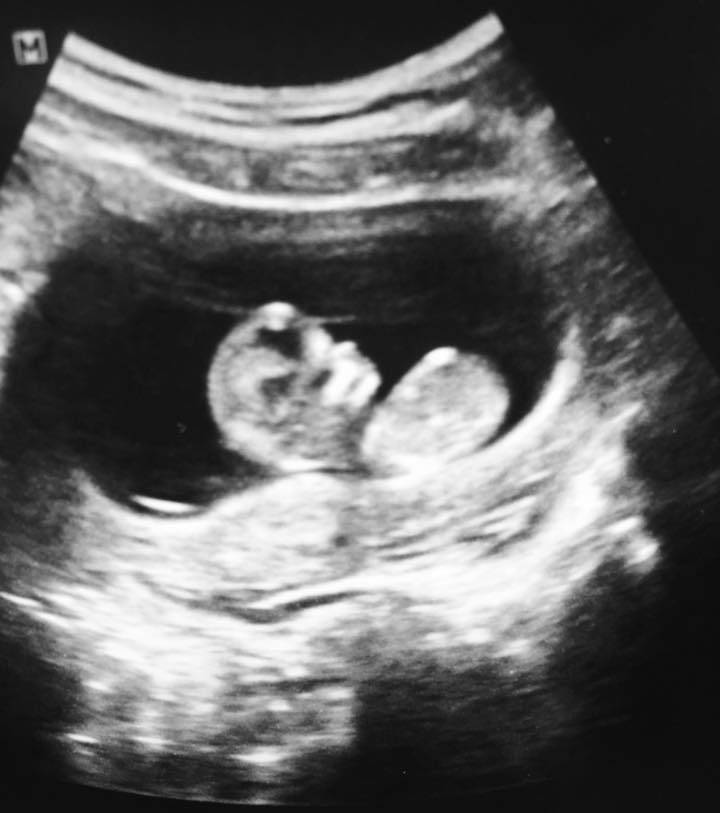

Un test di gravidanza ha confermato che era incinta.

“I dottori non ci avevano dato nemmeno una minima possibilità. Ci avevano detto che era impossibile.”

“Per noi era un vero miracolo“.